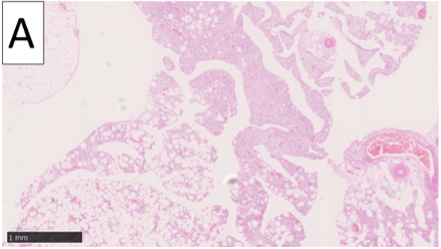

A 71-year-old man presented with a slow-growing subcutaneous tumor (prevalent since 6 years of age) on the left posterior neck. The patient had no previous relevant medical history. On physical examination, a 4- × 3-cm tumor that was elastic, soft, and somewhat hypermobile (Figure 1A) was revealed. There was no pain, redness, or elevated temperature in or around the tumor site. Magnetic resonance imaging (MRI) showed a heterogeneous internal structure on T1-weighted and T2-weighted images (Figure 1B). No significant lymphadenopathy was found. During surgery, an incision was made directly on the tumor, and the tumor was removed along the excised skin in a spindle shape (Figure 2). Histopathological examination using hematoxylin-eosin staining showed mature adipocytes, spindle cell proliferation (Figure 3A), and CD34 positivity (Figure 3B). No nuclear pleomorphism or mitotic figure was observed. The patient was diagnosed with spindle cell lipoma (SCL). There has been no pain or tumor recurrence 4 months postsurgery.

SCL is generally considered to be definitively diagnosed by histopathological examination. It is characterized by the proliferation of spindle-shaped cells, thick collagen bundles, mucous matrix in the interstitium, and scattered mast cells, which are composed of mature adipocytes.⁵ It is also characterized by CD34 positivity of spindle-shaped cells on immunohistochemical staining.6,7